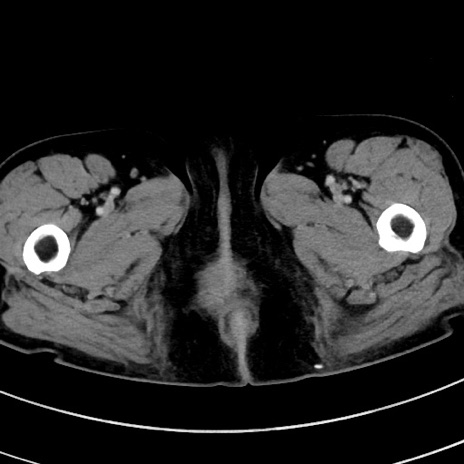

症例9(横断像)

【症例】 60歳代女性

【主訴】むかつき、みぞおちの痛み

【現病歴】3日前よりむかつきがあり、食事がとれない。

【既往歴】糖尿病

【身体所見】発熱なし、心窩部圧痛軽度あるも、腹膜刺激症状なし。

【データ】WBC 7400、CRP 1.92